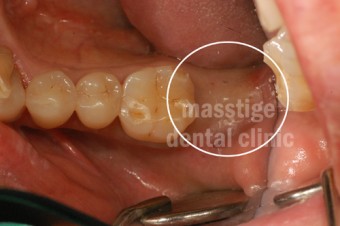

어금니 임플란트 전후 증례

치료 전 치아상태 : 어금니 1개를 상실한 상태

치료 진행 : 임플란트 1개 수술 진행